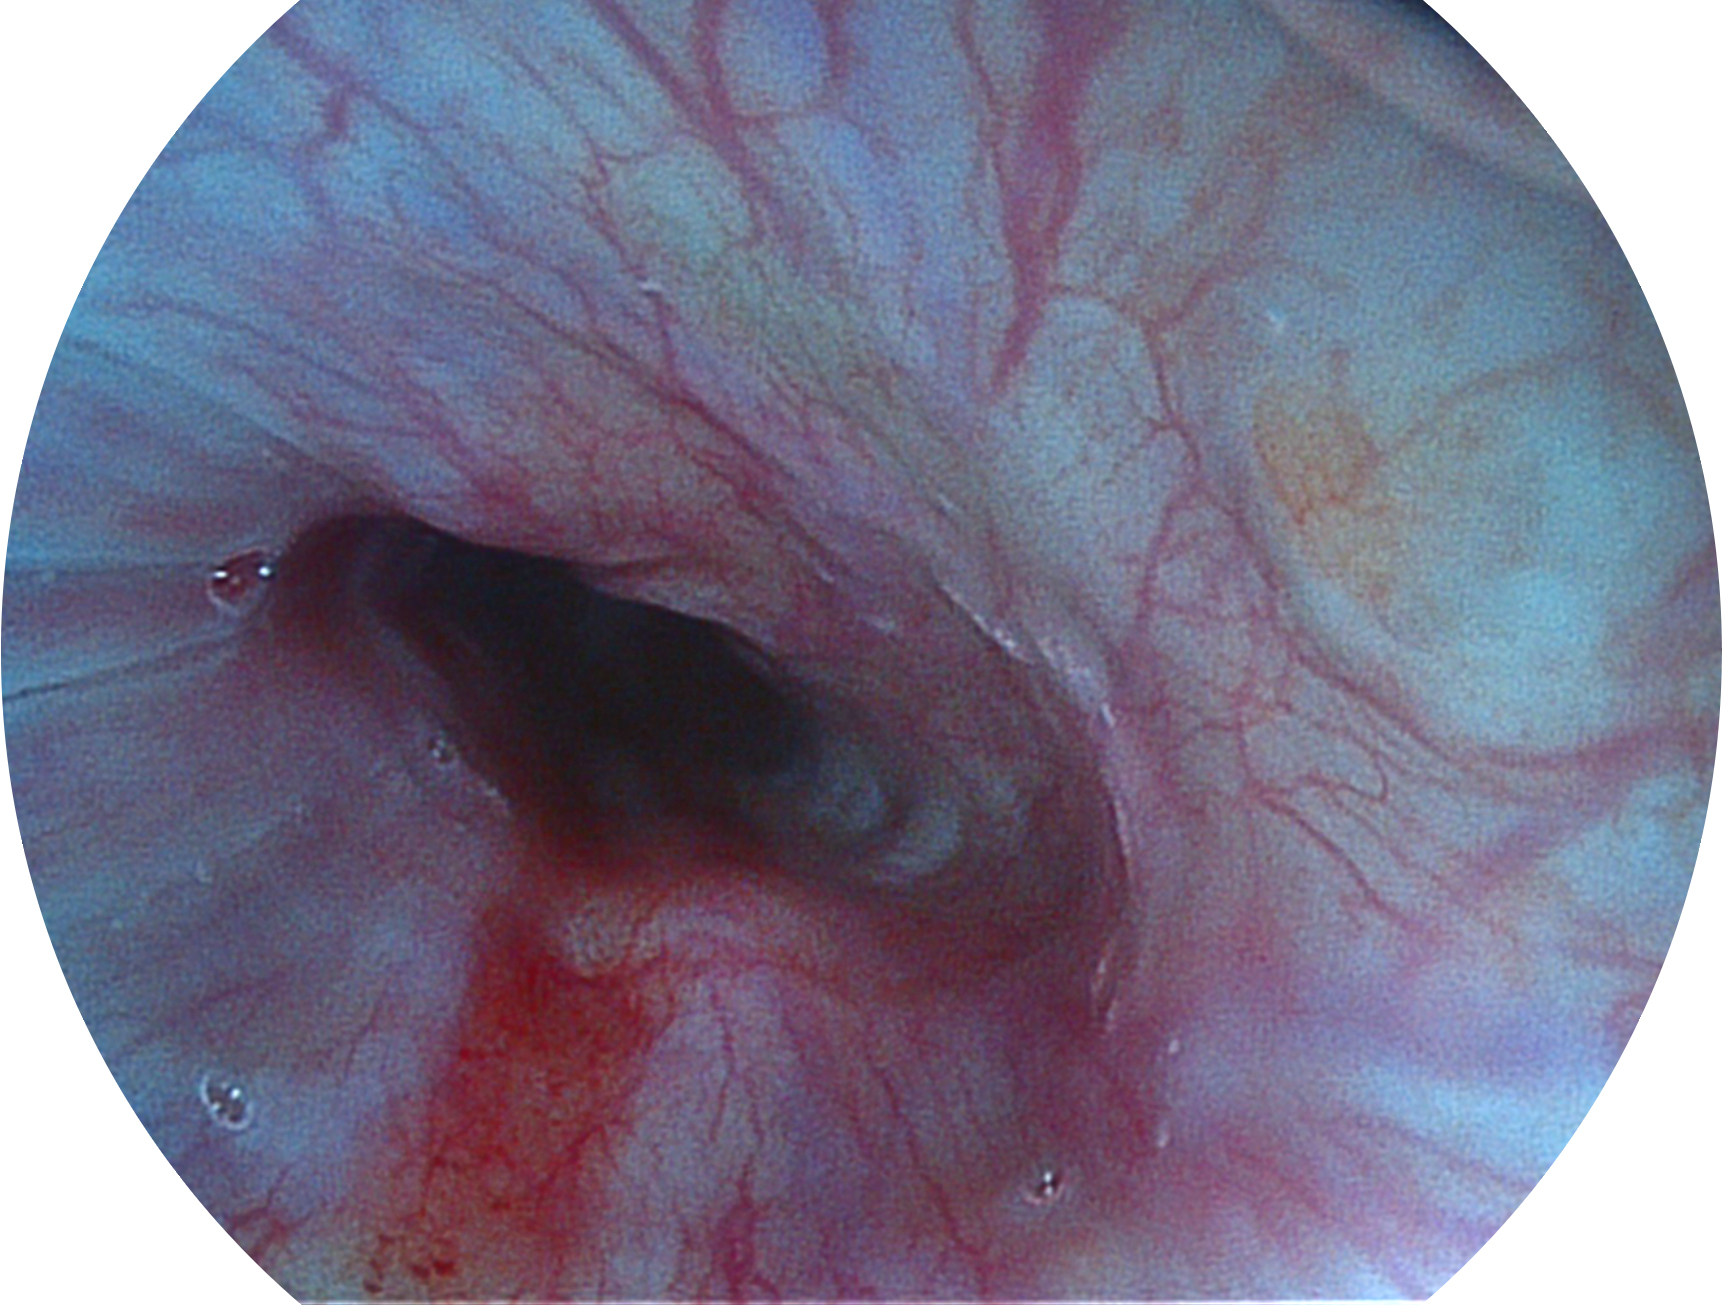

開立新開發(fā)的內(nèi)鏡染色技術(shù),主要是基于多波長LED 光源的開發(fā),VLS-55Q 四波長LED 光源是由四個不同顏色的LED光按照相應(yīng)照明模式所規(guī)定的特定發(fā)光比例進行合束后形成,合束后形成的照明光的光譜由紅光、綠光、藍光及藍紫光這四個不同的波段范圍構(gòu)成。具有更高光譜自由度,通過光譜比例的控制,實現(xiàn)了聚譜成像技術(shù),英文全稱為“Spectral Focused Imaging, SFI”,縮寫為“SFI”和光電復(fù)合染色成像技術(shù),英文全稱為“Versatile Intelligent Staining Technology, VIST”,縮寫為“VIST”。